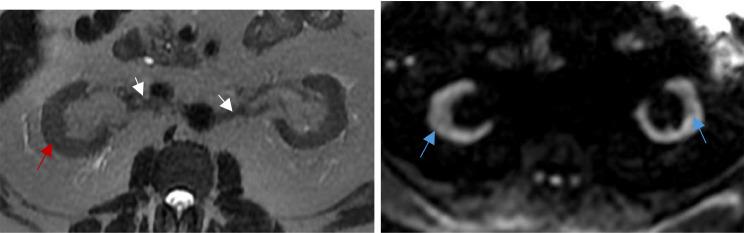

Radiology of fibrosis part III: genitourinary system.

Fibrosis is a pathological process involving the abnormal deposition of connective tissue, resulting from improper tissue repair in response to sustained injury caused by hypoxia, infection, or physical damage. It can impact any organ, leading to their dysfunction and eventual failure. Additionally, tissue fibrosis plays an important role in carcinogenesis and the progression of cancer.Early and accurate diagnosis of organ fibrosis, coupled with regular surveillance, is essential for timely disease-modifying interventions, ultimately reducing mortality and enhancing quality of life. While extensive research has already been carried out on the topics of aberrant wound healing and fibrogenesis, we lack a thorough understanding of how their relationship reveals itself through modern imaging techniques.This paper focuses on fibrosis of the genito-urinary system, detailing relevant imaging technologies used for its detection and exploring future directions.

纤维化是一种病理过程,涉及结缔组织的异常沉积,是由于缺氧、感染或物理损伤引起的持续损伤导致的组织修复不当引起的。它可以影响任何器官,导致其功能障碍和最终衰竭。此外,组织纤维化在致癌作用和癌症进展中起着重要作用。早期准确诊断器官纤维化,并定期进行监测,对于及时进行疾病修饰干预至关重要,最终可以降低死亡率并提高生活质量。虽然已经对异常伤口愈合和纤维化发生进行了广泛的研究,但我们对它们之间的关系如何通过现代成像技术表现出来仍缺乏全面的了解。本文重点介绍了生殖泌尿系统的纤维化,详细介绍了用于检测的相关成像技术,并探讨了未来的方向。